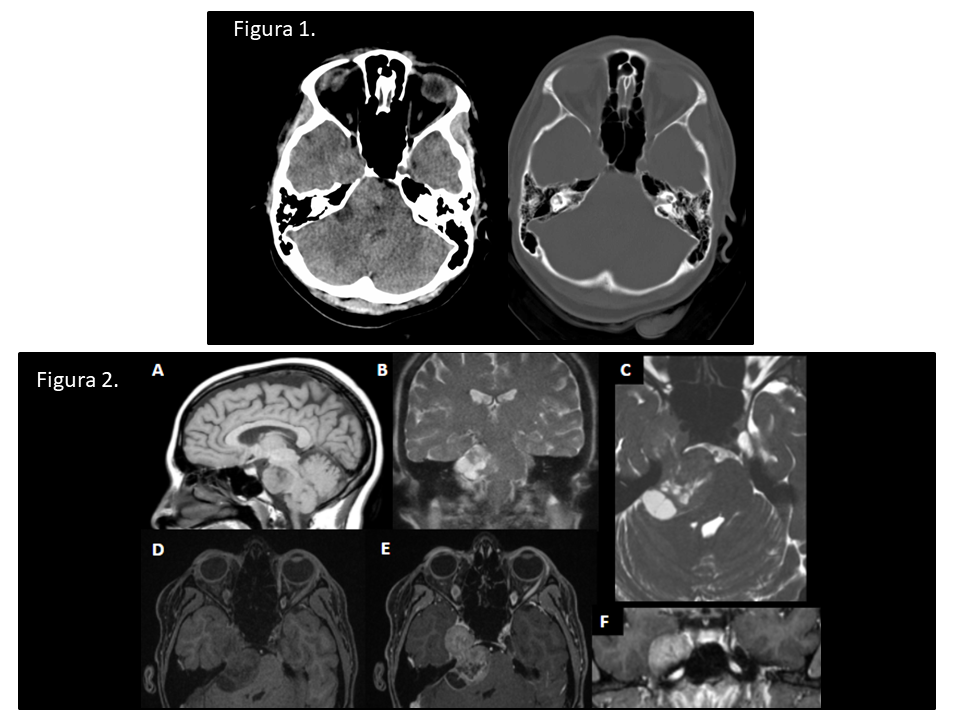

Figura 1. TC axial sin contraste IV. Masa extraaxial localizada en la cisterna prepontina con extensión paraselar derecha al cavum de Meckel. Comprime y desplaza protuberancia y deforma 4º ventrículo. Asocia remodelado óseo.

Figura 2. Imágenes de RM. Masa bilobulada en ángulo pontocerebeloso y paraselar derecha con áreas quísticas. No se identifica edema ni infiltración de estructuras adyacentes.

A. T1 axial sin contraste. Intensidad de señal intermedia.

B. T2 coronal. Componente quístico de la lesión.

C. FIESTA axial. Se identifica una hendidura de LCR que separa la vertiente posterior de la masa de la protuberancia. Vemos la constricción característica de la masa a su paso por el porus trigéminus. En el lado izquierdo se identifica el nervio trigémino contralateral sano entrando al cavum de Meckel relleno de LCR.

D y E. FAME axial pre- y postcontraste. Realce intenso tras la administración de contraste.

F. FAME coronal post-contraste. Ocupación del cavum de Meckel derecho; izquierdo de apariencia normal.